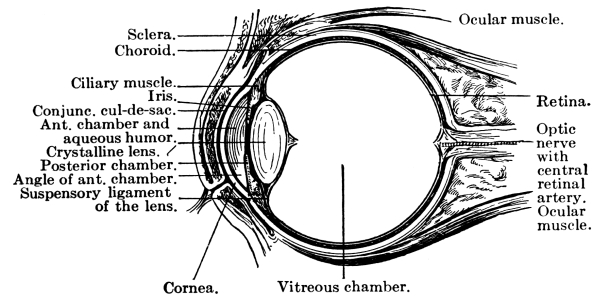

The Nose, 57—The Sense of Smell, 58—The Mouth, 59—The Hyoid Bone, 60—The Teeth, 60—The Sense of Taste, 61—Salivary Glands, 61—The Tonsils, 62—The Ear, 63—Eustachian Tubes, 63—Sensation of Hearing, 65—The Eye, 66—Lachrymal Gland, 68—Coats of the Eye, 68—Light Rays and Sight, 70—Accommodation, 72—Color Perception, 73. |